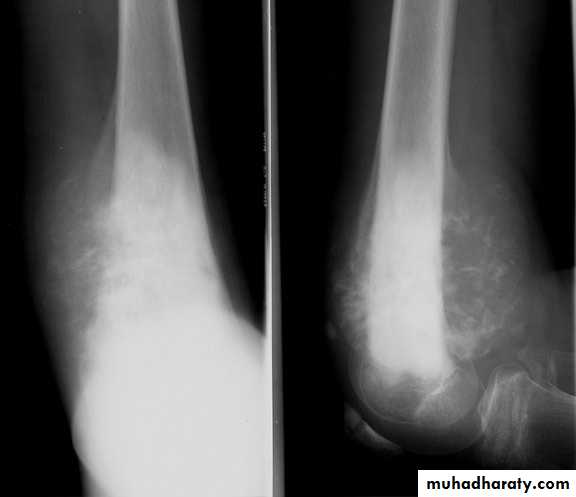

Ewing sarcoma

Highly malignant

Histology : small round cells25 % metastasis at presentation

C/F

Age 10 -25 yr

Pain

SwellingGeneralized illness & fever

Pathologic # rare

XR

Diaphyseal lesion

Tibia & fibula more common

New bone formation multiple layers onion – peel appearanceRx

CT + surgery

5 yr survival : 60 %